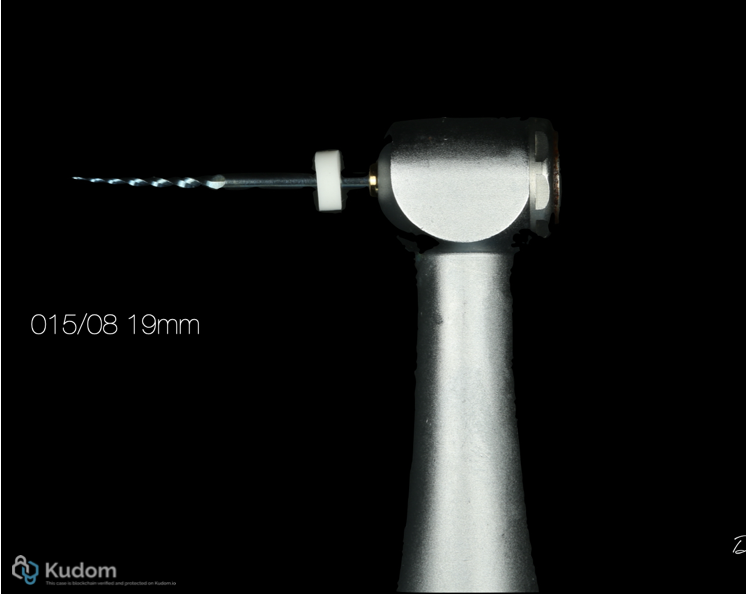

Fig. 11

Assorted file: 15/08 - 19mm